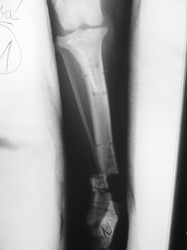

PRÁCTICAS CURSO DE FIJACIÓN EXTERNA PERFECCIONAMIENTO.

Híbrido.